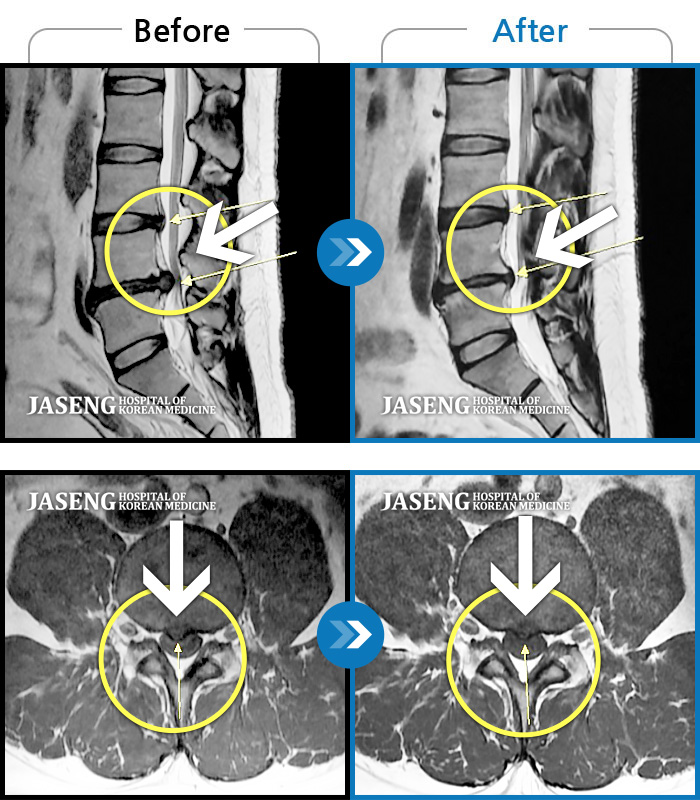

Before

After

환자에게 사전 동의를 받아 동일 조건에서 촬영되었습니다.

개인에 따라 치료 후 부작용이 발생할 수 있으니 의료진과 상담 후 치료를 진행하시기 바랍니다.

양쪽 허리와 골반 통증, 걸을 때 우측 다리 당김 및 통증

허리 좌측 골반에서 발목으로 통증, 저린감, 쥐나는 증상